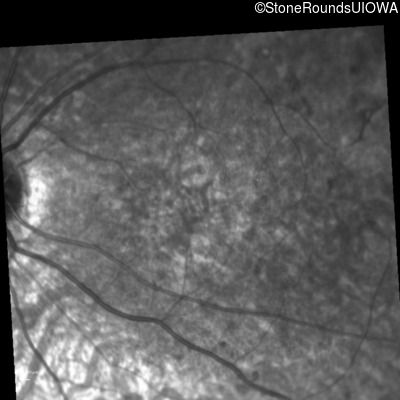

Visit at age: 8 years

Fundus Photography - Right - 5/200

Exemplar